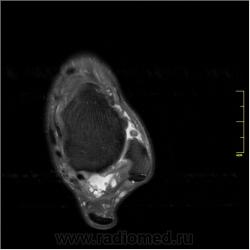

Я считаю, что присутствуют добавочные кости голеностопного сустава: os trigonum, os talus secundarius, os subfibulare, окруженные выпотом, вероятно, реактивного характера в результате избыточной нагрузки.

Есть вопрос. Чем вызвано изменение интенсивности (выражаясь рентгеновским языком), помеченное желтой стрелкой?

Я полагаю, что это артефакт суммации. Субхондральный склероз есть, но он не выражен значительно.

Еще вопрос. Как расценить "мелкую" тень (язык рентгеновский) помеченную желтой стрелкой?.

Валентин Львович! Аналогично - эффект суммации, так прошел срез. Есть выпот, который "наложился" на кость. Это хорошо видно при просмотре полной серии. К сожалению, на сайте поместить полное исследование затруднительно, я поместил только наиболее важные (по моему мнению) срезы.

У меня встречный вопрос - почему на рентгене не видно мелкую добавочную кость рядом с малоберцовой (os subfibulare)?

Вот тут я ответить затрудняюсь, она видна только на одном срезе. Чаще всего то, что видно только на одном срезе, должно быть видно и на другом (параллельном или перпендикулярном), иначе это можно считать артефактом. В данном случае сказать действительно сложно.

А, вот вроде-бы, почти на уровне той "тени", и "гнездо - вырезка" имеется, или мне просто кажется? - желтая стрелка.

Я тоже считаю, что есть деформация края суставной поверхности. Может быть, в результате профессиональной деятельности. В любом случае, к клинической симптоматике это отношения наверняка не имеет.